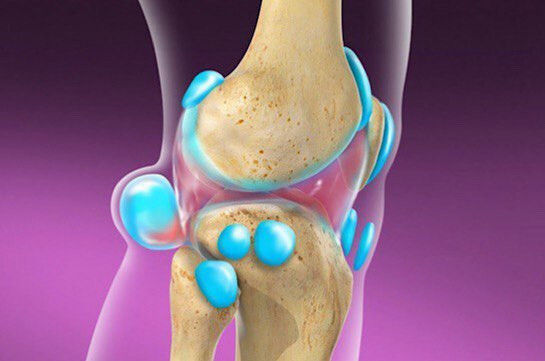

Բեյկերի կամ ծնկափոսային տարածության կիստան ծնկան հետևում հեղուկով լցված գոյացություն կամ այտուց է:

Այն սովորաբար առաջանում է՝ պայմանավորված ծնկան հոդի ավելցուկային հեղուկով: Հեղուկի քանակի ավելացման հետևանքով վերջինս ճնշում է հոդաշապիկի հետին պատը և առաջացնում ճողվածք՝ հեղուկով լցված պարկ կամ կիստա:

Բեյկերի կիստան կարող է ուղեկցվել ծնկան հոդի բորբոքմամբ կամ փափուկ վնասումով, ինչպիսին է հոդաշապիկի պատռվածքը: